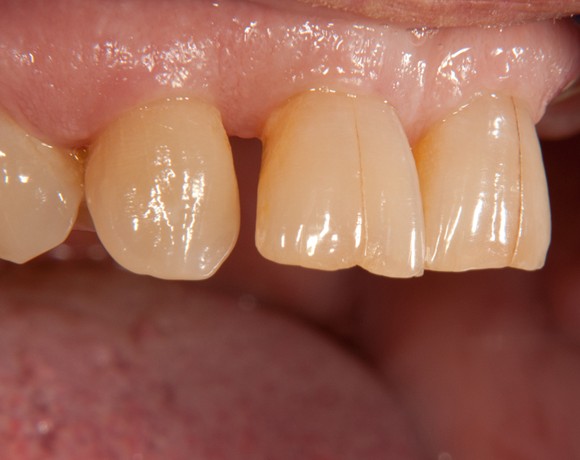

Bei dieser Patientin mussten die Zähne 22,26 und 27 aus parodontalen Gründen entfernt werden. Nach Extraktion der Zähne 22 und 26 wurden sofort in die Extraktionsalveolen die Implantate gesetzt. Zahn 27 war bereits sechs Monate zuvor extrahiert worden und die Knochenwunde gut ausgeheilt. Das geringe Knochenangebot wurde mit einem internen Sinuslift ausgeglichen. Im Bereich des Zahnes 23 wurde noch ein weiteres Implantat gesetzt. Da der Zahn 12 nicht angelegt und die Symetrie auf dieser Seite gestört war, wurden die Zähne 11 und 13 mit Teilkronen versorgt, um die Lücken zu schließen der Zahn 13 zu 12 umgebaut.